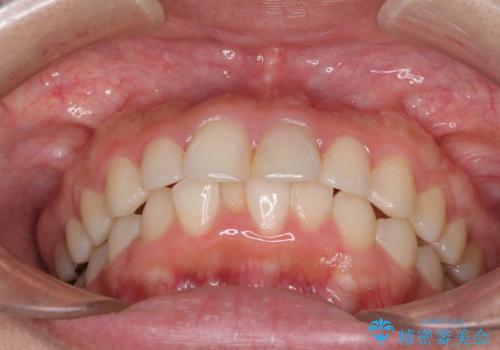

矯正治療の後戻り ガタガタになった前歯の部分矯正

- 以前の矯正治療の後戻りを気にして来院された患者様です。

下顎前歯にデコボコがあるため、ワイヤー矯正により改善することとしました。

もう少しデコボコを改善したかったのですが、ご本人の希望もあり、装置を除去しました。

後戻りを防止するため、舌側を細いワイヤーによる保定を行いました。